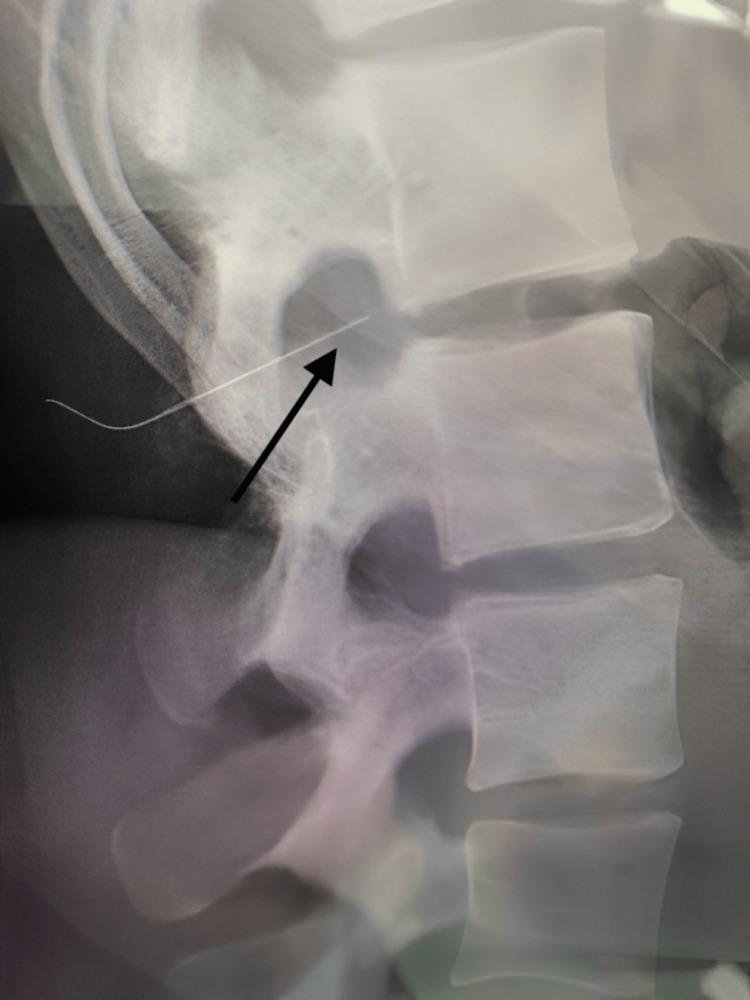

Spinal anesthesia is the most common mode of anesthesia utilized during caesarian sections worldwide. Despite its many advantages over general anesthesia in the pregnant cohort, uncommon and even catastrophic complications could occur due to patient-related, equipment-related, and procedure-related complications. One such uncommon event of a broken spinal needle during failed spinal anesthesia for a caesarian section and subsequent successful management is described here.

脊髓麻醉是全球剖宫产手术中最常用的麻醉方式。尽管在孕妇群体中,它相对于全身麻醉有诸多优势,但由于患者相关、设备相关和操作相关的并发症,仍可能发生罕见甚至灾难性的并发症。本文描述了一例剖宫产脊髓麻醉失败时脊髓穿刺针折断,随后成功处理的罕见事件。